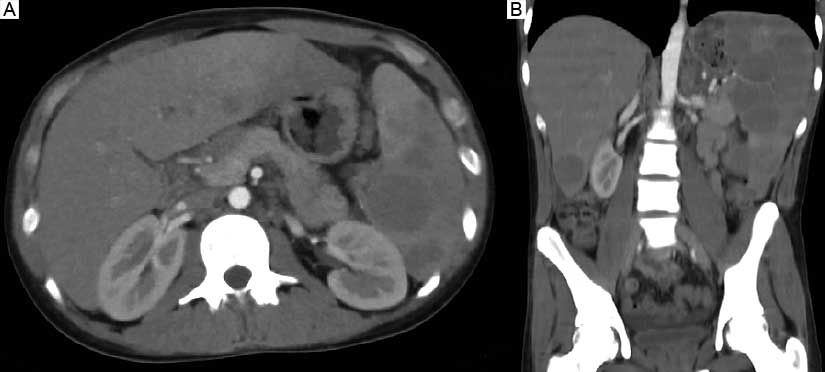

Al ingresar al servicio de Urgencias, el paciente presentaba fiebre de 39.3 °C, malestar general, cansancio, diarrea en escasa cantidad, sin moco y sin sangre, acompañada de dolor abdominal leve en cuadrante inferior izquierdo. Se documentó hemoglobina de 9.5 g/dL, leucocitos 5.13 x 103/mm3, plaquetas de 124 000 cel/mm3, globulinas 4.2 g/dL; creatinina 0.7 mg/dL, bilirrubina total 0.7 g/dL, albúmina 2.9, alanino aminotransferasa 28 UI/L, aspartato aminotransferasa 105 UI/L, fosfatasa alcalina 89 UI/L; cloro 97 mEq/L, potasio 4.5 mEq/L, sodio 139 mEq/L. La prueba de VIH resultó reactiva, así como los marcadores tumorales beta 2 microglobulina 20 000 ng/mL, alfafetoproteína 0.61 ng/mL y antígeno carcinoembrionario 0.99 ng/mL. Asimismo, se identificó una carga viral para VIH de 100 034 cp/m y de CD4 76 cel/mcL (5%). Se repitió el ultrasonido de abdomen, se describió enfermedad quística hepatoesplénica. Se realizó tomografía computarizada abdominopélvica, su reporte fue hepatoesplenomegalia, adenopatías retroperitoneales e inguinal y líquido libre en cavidad abdominal (figura 1). Se inició cobertura amplia con meropenem y vancomicina ante la sospecha de abscesos hepáticos y esplénicos.

El involucro esplénico se puede presentar con una masa o con esplenomegalia. Es importante mencionar que la sola esplenomegalia no siempre equivale a infiltración maligna del linfoma.10 Las imágenes características incluyen un agradamiento difuso o lesiones únicas o multifocales que pueden ser heterogéneas, así como con necrosis central. Igualmente en el hígado puede haber lesiones parenquimatosas hipodensas únicas o múltiples, así como infiltración periportal.11